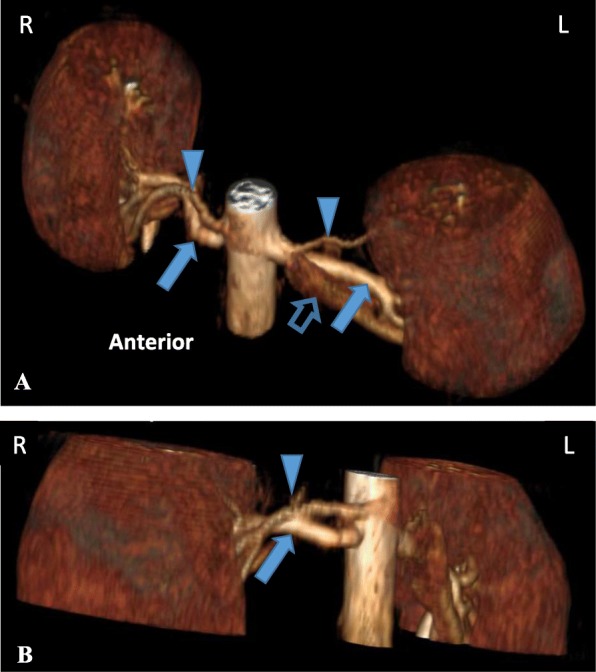

Fig. 1.

3-dimensional reconstruction of contrasted renal MRA. (a) Left anterosuperior oblique view showing bilateral accessory renal arteries arising above the main renal arteries (b) Right oblique view demonstrating the right renal accessory artery. (Arrowhead = accessory renal artery; closed arrow = main renal artery; open arrow = renal vein)

A 21 year old woman with no prior medical illness presented with epistaxis and raised blood pressure of 200/142 mmHg. She consumes 20 unit of alcohol per week and is a smoker of 1 pack year. On examination, she was obese with a body mass index (BMI) of 29.7 kg/m2. Physical examination was otherwise unremarkable with no hirsutism nor cushingnoid features. There was no abdominal bruit, radio-radial, or radio-femoral delay. Laboratory investigation at presentation showed hypokalemia (potassium 2.6 mmol/L) and alkalosis. Renal function, liver function, thyroid function, fasting blood glucose and lipid profile were within normal limits. 8 am cortisol was 17.11 μg/dL. Echocardiography showed asymmetrical left ventricular hypertrophy. She was treated with prazosin 2 mg tds and amlodipine 10 mg daily as well as oral potassium chloride 1.2 g od to maintain normal blood pressure and potassium level. Further work up after normalization of potassium revealed secondary hyperaldosteronism with elevated plasma aldosterone 1100 pmol/L (Reference range 102–858) and direct plasma renin 230.10 mIU/L (Reference range 4.2–59.7); giving a aldosteorone renin ratio (ARR) of 5 pmol/mIU. There was no evidence of renal artery stenosis on renal Doppler study. Renal magnetic resonance angiography (MRA) showed normal renal arteries bilaterally but bilateral accessory renal arteries were seen superior to the main renal arteries (Fig. 1). Renal angiography had no evidence of stenosis in the main or the accessory arteries bilaterally. In view of the absence of demonstrable stenosis for intervention, the patient was put on medical therapy. Her blood pressure was subsequently controlled on spironolactone 75 mg daily and amlodipine 10 mg daily.